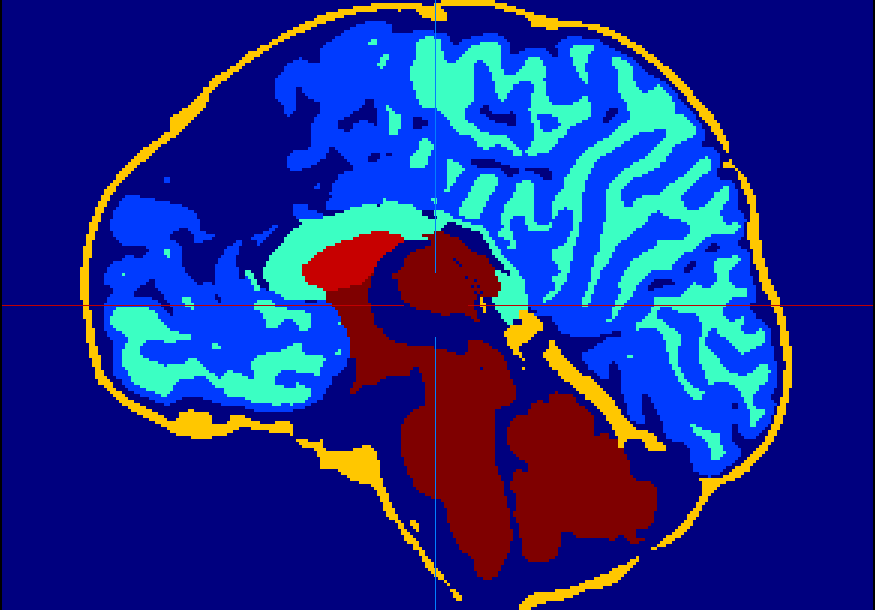

The dataset consisted of 70 3D T2-weighted brain MRI scans publicly available from the dHCP neonatal cohort. The segmentation maps had 10 classes, corresponding to: zero-pixel background, cerebrospinal fluid (CSF), cortical grey matter (cGM), white matter (WM), background bordering brain tissues, ventricles, cerebellum, deep grey matter (dGM), brainstem, and hippocampus. The scans covered an age range of 24.3-42.2 weeks. The data was available in NIfTI format; Figure 1 shows an example scan and corresponding tissue labels. We carried out a pre-processing step where each scan was independently normalised to zero-mean and unit-variance.